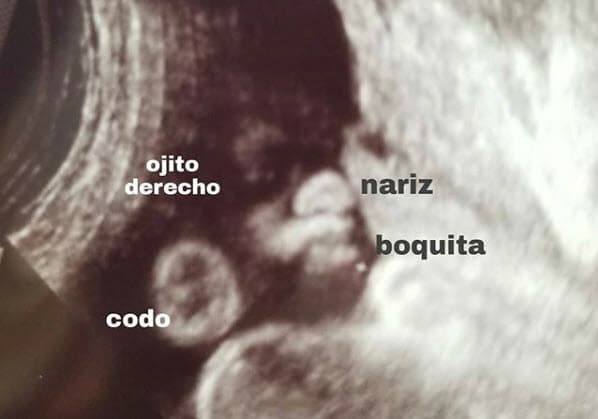

Con esta imagen, el 2 de octubre de 2017 anunció su embarazo en Instagram: "Estoy a ley de 2 semanas para terminar el crítico primer trimestre, pero ya hoy me siento fuerte para testificar nuevamente que en mi vida Dios sigue teniendo el control. Estamos inmensamente felices por nuestro bebé pero sobre todas las cosas porque una vez más y siempre, frente a cualquier situación damos la gloria a él, y he aquí nuestra promesa para el rey".